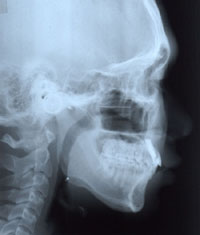

15세 7개월 된 남학생이 상악전치부 spacing을 주소로 내원하였다. 방사선사진을 촬영하고 상·하악 인상을 채득한 후 통상적인 방법으로 교정진단을 한 결과 다음과 같은 problem을 갖는 것으로 진단되었다 (그림 1,2).

그림 2. 내원시 측모두부방사선사진과 파노라마 사진을 통해 결손부위에 인접한 치아들의 위치를 파악할 수 있다.

측모두부방사선규격사진에서는 상악골이 다소 돌출되어 있는 양상을 보이고 있는 것 외에는 두드러진 문제가 보이지 않았다. 파노라마 사진에서 상악중철치의 치근이 짧은 것이 눈에 띄었으며 좌우 견치가, 특히 좌측 견치가 견치위치라기보다는 측절치 위치에 자리잡은 것으로 나타났다. 석고모형 분석 결과 상악의 공간 양은 약 16mm로 측정되었으며 개개 치아크기를 평균치와 비교시 상악 양 중철치가 두드러지게 작은 것을 알 수 있었다. 반면 하악은 정상적인 배열을 보였다. 상·하악 교합 분석시 좌측은 정상적인 Cl I을 보였으나 하악 치열 정중선의 우측 편위와 함께 우측교합은 Cl II를 나타내었다. OB과 OJ은 3.0과 3.5mm로 정상보다 1.0 또는 1.5mm 큰 양상을 보였다 (그림 2,3).